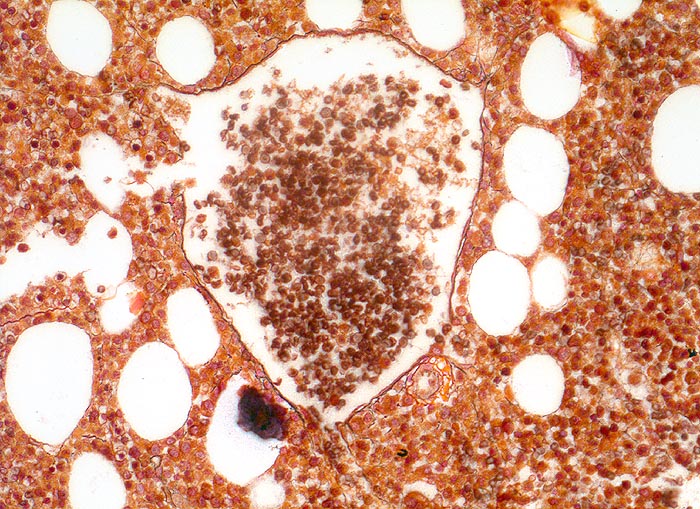

Die Erkrankung ist charakterisiert durch Knochenmarkfibrose, Hepato-Splenomegalie und extramedulläre Blutbildung. Diese findet sich am häufigsten in Leber und Milz, seltener in Lymphknoten, Nieren, Nebennieren, Dura mater, Gastrointestinaltrakt, Lunge, Mamma oder Haut. Blut und Knochenmark sind immer involviert. Die Krankheit entwickelt sich über ein initiales präfibrotisches Stadium mit hyperzellulärem Knochenmark zum fibrotischem Stadium (vorliegendes Präparat). Das fibrotische Stadium ist gekennzeichnet durch eine Vermehrung von Reticulin- und/oder Kollagenfasern und oft einer Knochenneubildung (=Osteomyelosklerose). Die Zellularität des Knochenmarks ist dann vermindert und dilatierte Marksinus enthalten intraluminale Blutbildungsherde. Es besteht eine auffallende Proliferation von Gruppen bildenden atypischen Megakaryozyten.

• Dilatierte Sinusoide mit intrasinusoidaler Blutbildung.

• Vermehrung von atypischen, in Gruppen liegenden Megakaryozyten mit abnorm lobulierten Kernen.

• Nacktkernige (zytoplasmaarme) und vergrösserte Megakaryozyten.